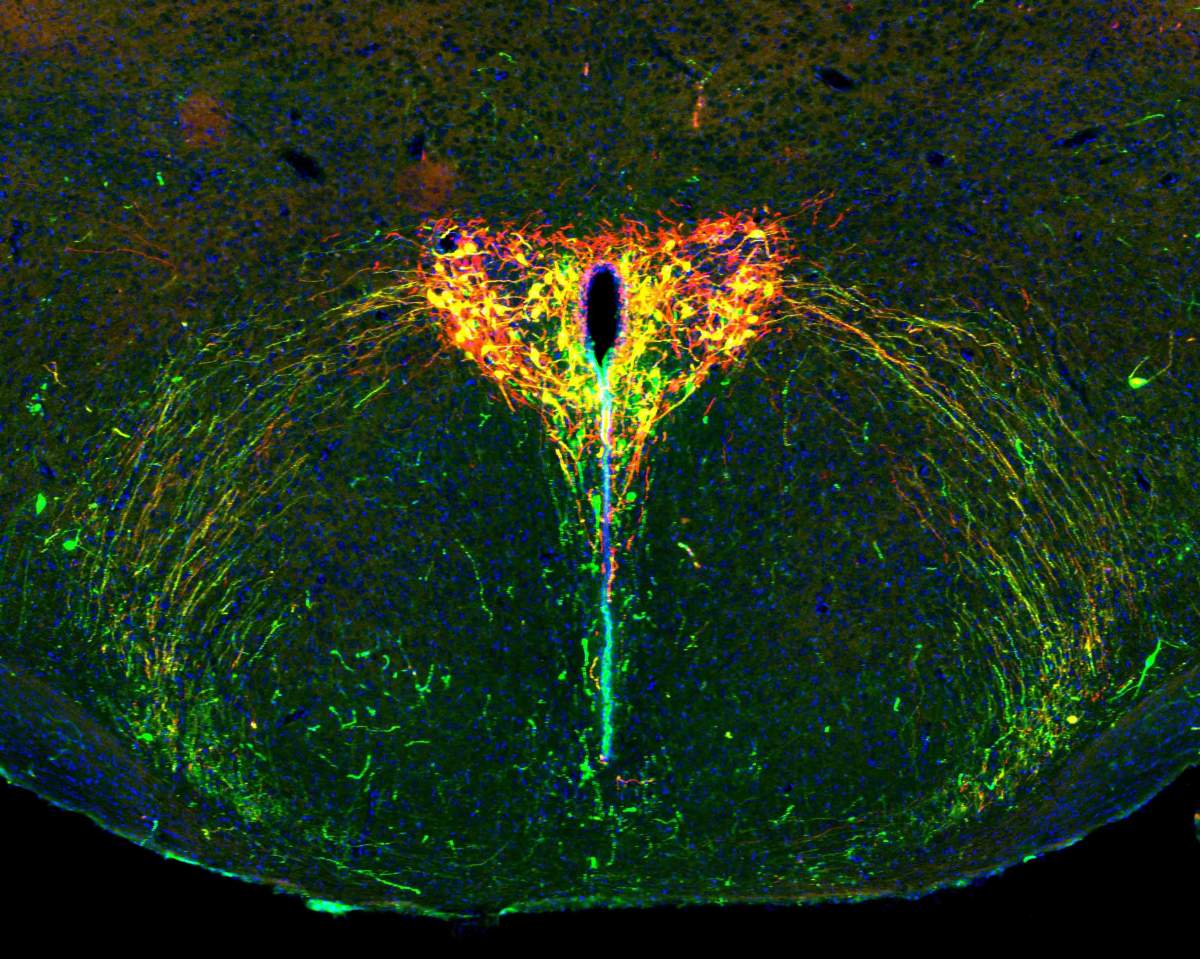

Le cerveau en développement d’un souriceau âgé de deux semaines sous le microscope. Le système de l’ocytocine apparaît en vert, la protéine photosensible en rouge et les cellules qui contiennent les deux apparaissent en jaune. Les noyaux cellulaires sont en bleu.